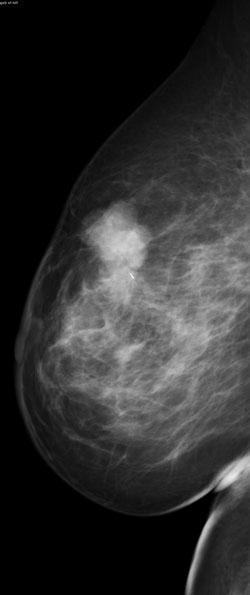

Palpable mass in the upper breast

Palpable mass in the upper breast shown on mammography to be irregular.

MR MIP image

MR MIP image again shows the irregular mass in the upper outer breast. Histology revealed a T2, N0, M0 invasive ductal carcinoma (ER/PR +, Her-2 neu -) and high-grade ductal carcinoma in situ.